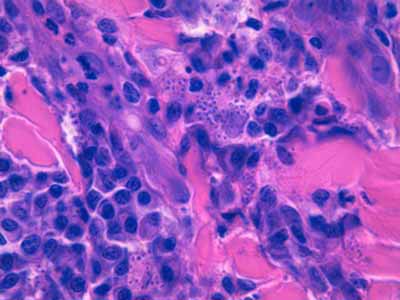

Photo 11 (Hémalun-Eosine X400) : Vue rapprochée d’une pustule intra-épidermique sous-cornée :

son toit est fragile formé de fines lamelles de kératine; son plancher épidermique

est le siège d’une forte exocytose de cellules inflammatoires; elle renferme

des granulocytes et quelques cellules épithéliales arrondies de type acantholytique.

Légendes de la Photo 11 :

- Pointes de flèche jaune : toit de la pustule intra-épidermique sous-cornée, composé de fines lamelles de kératine orthokératosique alvéolaire

- Étoile rouge évidée : cellule épithéliale acantholysée (la plus grande

- Pointes de flèche turquoise : elles délimitent le contour du plancher de la pustule intra-épidermique sous-cornée

- Flèche orange : spongiose ou œdème intercellulaire

- Étoiles vertes évidées : granulocytes dans le contenu de la pustule et en cours d’exocytose transépidermique dans le plancher épidermique

- Cercles jaunes : pustules micro-loculaires qui confluent en position sous-cornée pour former la pustule dont le plancher est matérialisé par les pointes de flèche turquoises

- Double flèche noire : épiderme

- Double flèche pointillée noire : derme

Photo 12 (Hémalun-Eosine X400) : Vue rapprochée du plancher d’une

pustule intra-épidermique sous-cornée : forte exocytose de granulocytes éosinohiles;

quelques cellules épithéliales s’arrondissent et se libèrent de leurs attaches

desmosomiales, rappelant une acantholyse intra-épidermique.

Légendes de la Photo 12 :

- Étoiles rouges : cellules épithéliales se détachant individuellement ou en petits groupes du plancher épidermique, leurs contours cytoplasmiques sont lisses, arrondis et leur noyau non pycnotique, suggérant une acantholyse intra-épidermique

- Étoiles vertes : granulocytes

- Double flèche noire : épiderme

- Flèches oranges : exocytose granulocytaire au sein du plancher épidermique conduisant à la formation de micro-pustules

Photo 13 (Hémalun-Eosine X1000 objectif à immersion) : Vue au fort

grossissement du plancher d’une pustule intra-épidermique sous-cornée :

forte exocytose de granulocytes éosinohiles; des cellules épithéliales de la couche

granuleuse au noyau bien visible, non pycnotique, s’arrondissent et se libèrent

de leurs attaches desmosomiales, rappelant une acantholyse intra-épidermique.

Légendes de la Photo 13 :

- Pointes de flèche jaune : toit de la pustule formée de kératine orthokératosique

- Flèche oranges : exocytose transépidermique de granulocytes éosinophiles

- Flèche jaunes : spongiose épidermique ou œdème intercellulaire

- Étoiles turquoises : granulocytes éosinophiles

- Cercles jaunes : cellules épithéliales se détachant individuellement ou en petits groupes du plancher épidermique (couche granuleuse), leurs contours cytoplasmiques sont lisses arrondis et leur noyau non pycnotique, suggérant une acantholyse intra-épidermique

- Étoiles rouges : érythrocytes

- Double flèche noire : épiderme